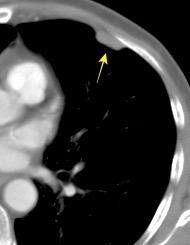

Tromboembolismo pulmonar.

Frecuencia del derrame:

Rx: 32%. TC: 47%

Unilateral. 85%

< 1/3 del hemitórax: 90%

Todos exudados

58% con eritrocitos

21% tabicación lo que causa demora en el diagnóstico

TEP. Empiema pleural. Atelectasia redonda

Porcel JM et al. Analysis of pleural effusions in acute pulmonary embolism: radiological and pleural fluid data from 230 patients. Respirology 2007/ Iguchi T et al. Desquamation of the subpleural lung parenchyma caused by empyema after pulmonary embolism: A case report. Respirol Case Rep. 2022 .